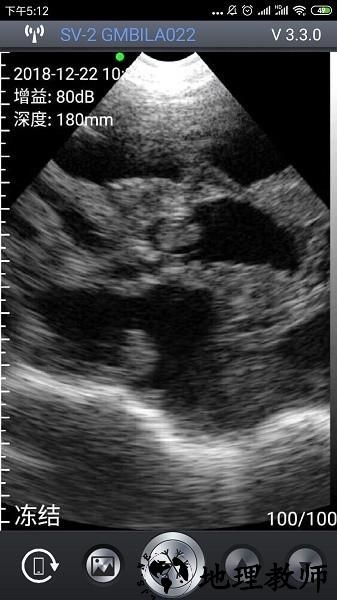

1、在进入APP后,屏幕左上角会显示当前时间、深度参数,若设备未连接或未启动探头,这些值将显示为--。

3、当探头正常工作且图像实时显示时,界面左上角会显示具体的增益,用户可据此调整图像清晰度与探测深度。

2、实时图像显示:即时呈现超声扫描画面,便于快速查看与初步判断检测结果。